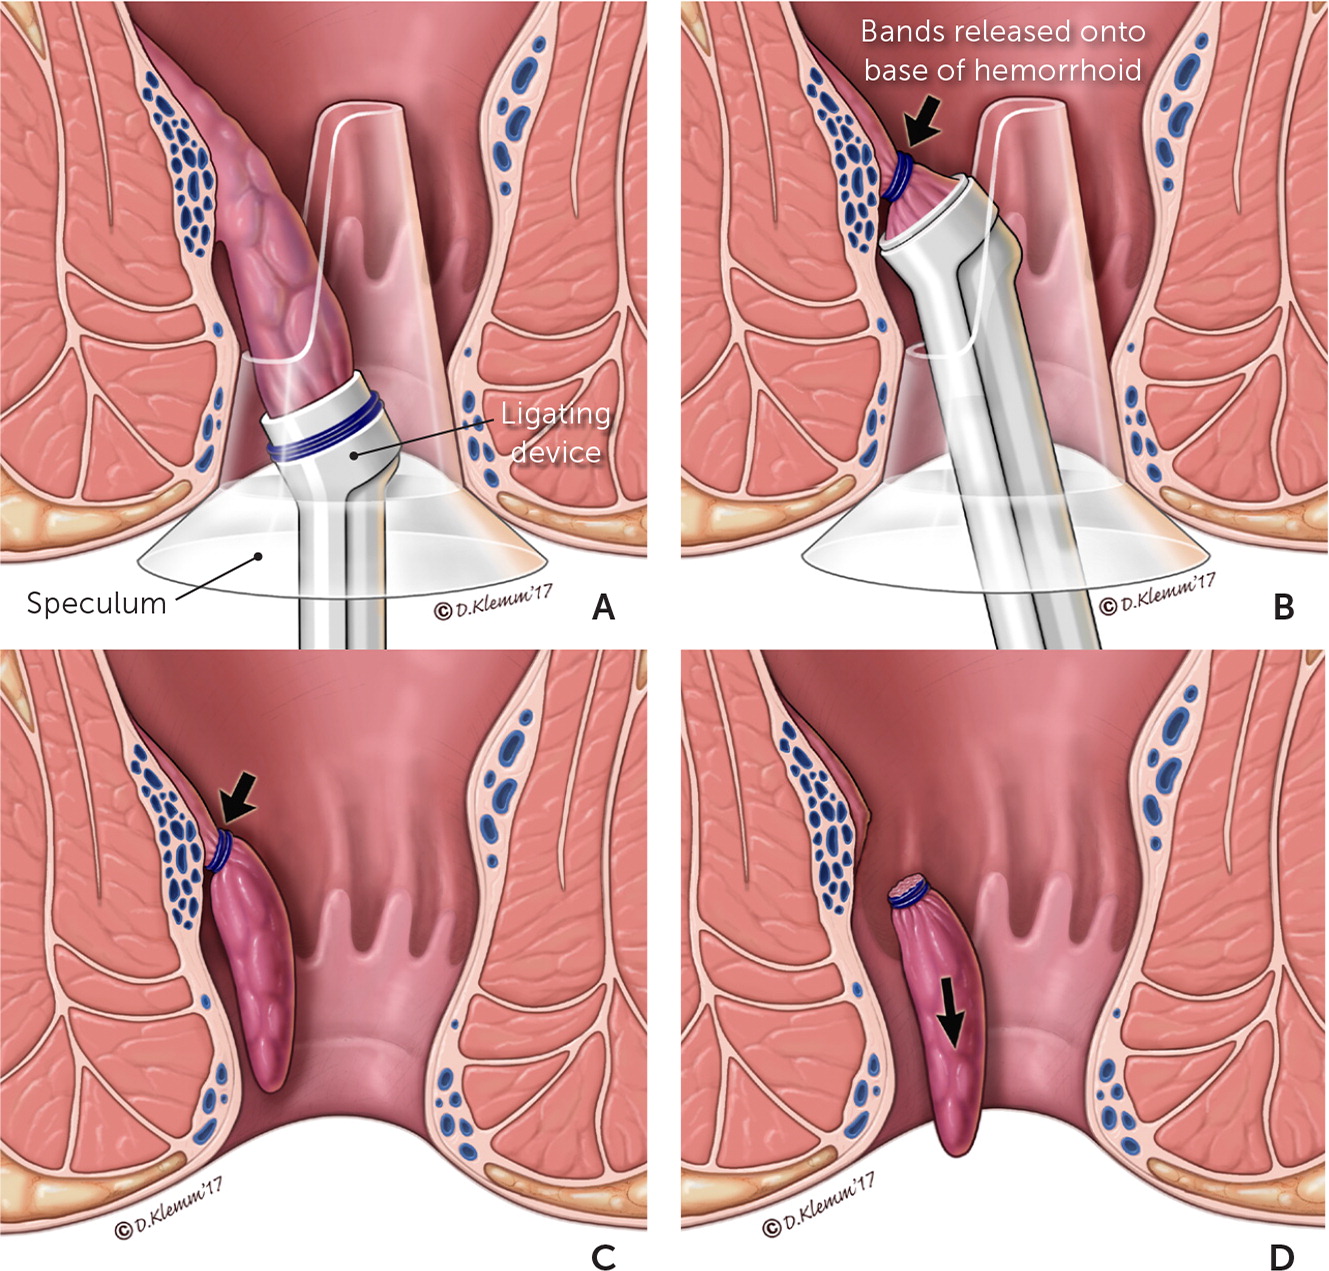

Overview

Package includes:

Days in hospital : 2 to 3 Days (For patient and one attendant)

Days in hotel : 7 Days (For patient and one attendant)

Room type in hospital : Shared

Room type in hotel : Private

Hotel category: Standard

Value added benefits of the Stapler Haemorrhoidectomy:

Ø Doctor consultation charges

Ø Lab tests and diagnostic charges

Ø Room charges inside hospital during the procedure

Ø Surgeon Fee

Ø Nursing charges

Ø Hospital surgery suite charges

Ø Anesthesia charges

Ø Routine medicines and routine consumables (bandages, dressings etc.)

Ø Food and Beverages inside hospital stay for patient and one attendant.

Extra benefits:

ü Interpreter

ü Visa assistance

Ø Site tourism of the city

Ø Follow up with the doctor

Ø Airport pick up and drop

Ø Free online consultation with the doctor

Ø Priority appointments with the doctor

Ø Room upgrade from sharing to private